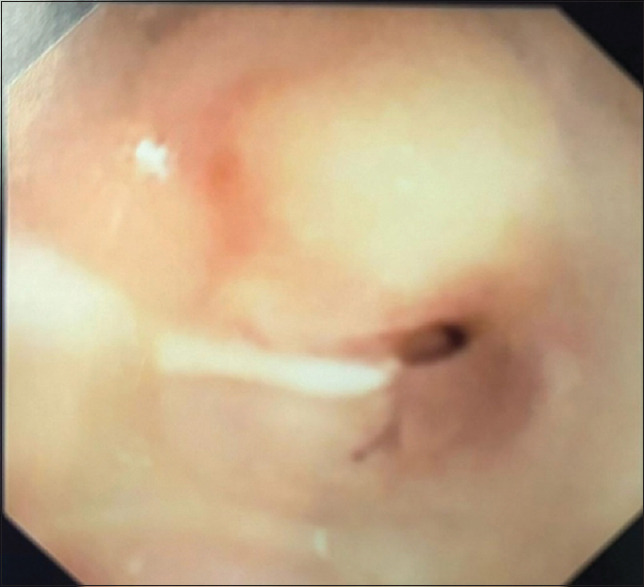

This is a case of a 3-year-old child who presented with long-segment tracheal stenosis (LSTS) and complex congenital cardiovascular disease for surgical intervention. The ideal operation for this child will include slide tracheoplasty and multiple cardiac lesion repairs. However, the low birth weight and extremely young age present a dilemma as to whether to perform total repair simultaneously or in stages. Age and weight by which the first surgical procedure was done, cardiovascular abnormality details, preoperative respiratory support, preoperative tracheobronchomalacia, cardiopulmonary bypass, the complexity of the surgery, and preoperative extracorporeal membrane oxygenation support are known to be predictive factors of long-term outcomes. Comparative studies between simultaneous and staged operations have shown that it is best to manage children with LSTS and complex cardiovascular anomalies in stages.

Abstract Image